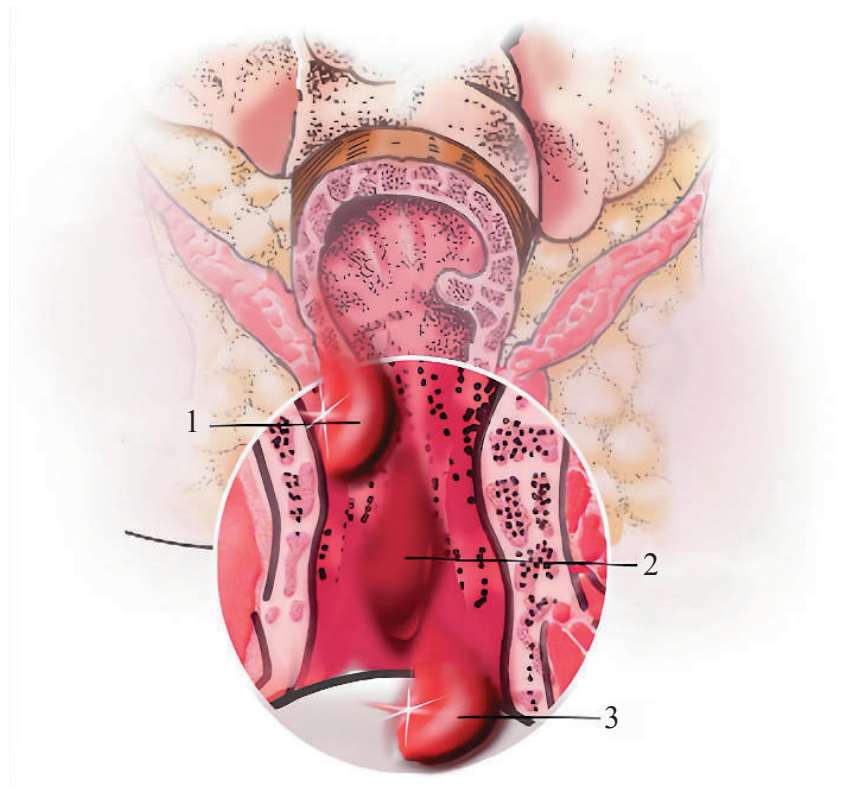

(1)痔静脉曲张:痔静脉曲张是最早比较系统解释痔生成的病因学说,虽然这一观点仍受争议,但从痔病研究进程来看,静脉曲张学说持续了相当长的时间,直到现在还影响着临床医生对其他痔病学说的接受度。从解剖学上看,人类直立行走时,肛门处在躯干最低位置。由于地球重力作用,以及门静脉及其属支无静脉瓣,造成肛门直肠区域静脉系统血液回流受到影响,痔上、痔下静脉丛淤血扩张形成隆起的静脉团(图 2—1)。另外,至今尚未发现动物在自然状态下产生痔的表现,这一现象似乎可以佐证直立行走给人类带来“痔”的事实,也让人很难完全回避“痔静脉曲张”对痔形成的影响。

图 2—1 痔静脉丛

1.直肠上静脉 2.髂内静脉 3.直肠下静脉 4.阴部内静脉 5.肛门静脉 6.痔外静脉丛7.痔内静脉丛 8.纵肌层 9.环肌层 10.黏膜 11.肛提肌